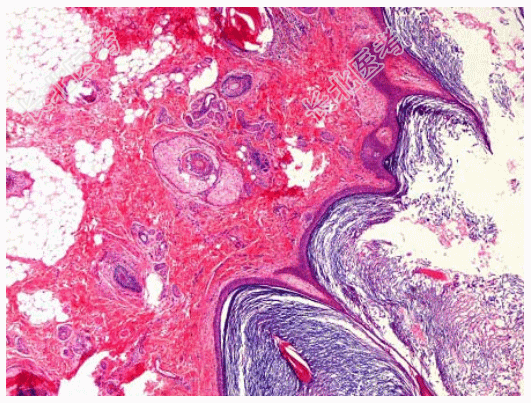

- [材料题] 患者女性,45岁,发现右下腹鸡蛋大肿物3月,行手术切除。大体见右卵巢囊性肿块5cm×5cm×4cm,包膜完整,切开内含大量皮脂、毛发,囊壁较光滑。显微镜下见角化鳞状上皮、丰富的皮脂腺、毛囊(如图)。临床诊断为卵巢成熟性囊性畸胎瘤。